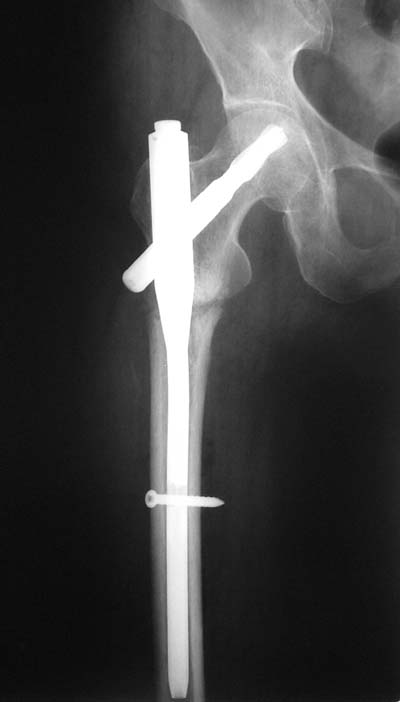

Присоединяюсь. Хотя посмотреть бы вторую проекцию.

И по фасу - шеечый винт можно бы и подлиннее.

АС> Дистальное блокирование провели правильно: статическое.

Нижний винт тут, насколько я понимаю, не особо нужен, поскольку проксимальный винт проходит через дистальный отломок.

Да наутро после операции. Все проксимальные фиксаторы рассчитаны на немедленную нагрузку, но при непременном условии - правильном расположении шеечного винта в шейке и головке.

Да? Качество рентгенограмм конечно неочень, но ведь это нестабильный перелом 31.А2.2, не так ли?